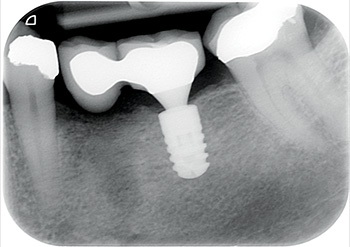

Fig. 5: Restoration PA.

Long Story Short: A Controversial Case?

Fig. 6: Restoration view.

Fig. 7: Restoration view in occlusion.

So, I placed an 8 mm-long Ankylos implant into her lower left first molar site. Three months later, the prosthodontist restored it with a cantilever bridge.

Well, Frances moved to the other side of the country, but I used to see her initially once a year and then every two years, free of charge, just so I could post updates of the case to Dentaltown. As you can see from the most current X-rays, not only has the implant survived, but the bone around the implant (what many worried would be overloaded and lost) looks even better in 2024 than it did in 2009 when the implant was first restored!